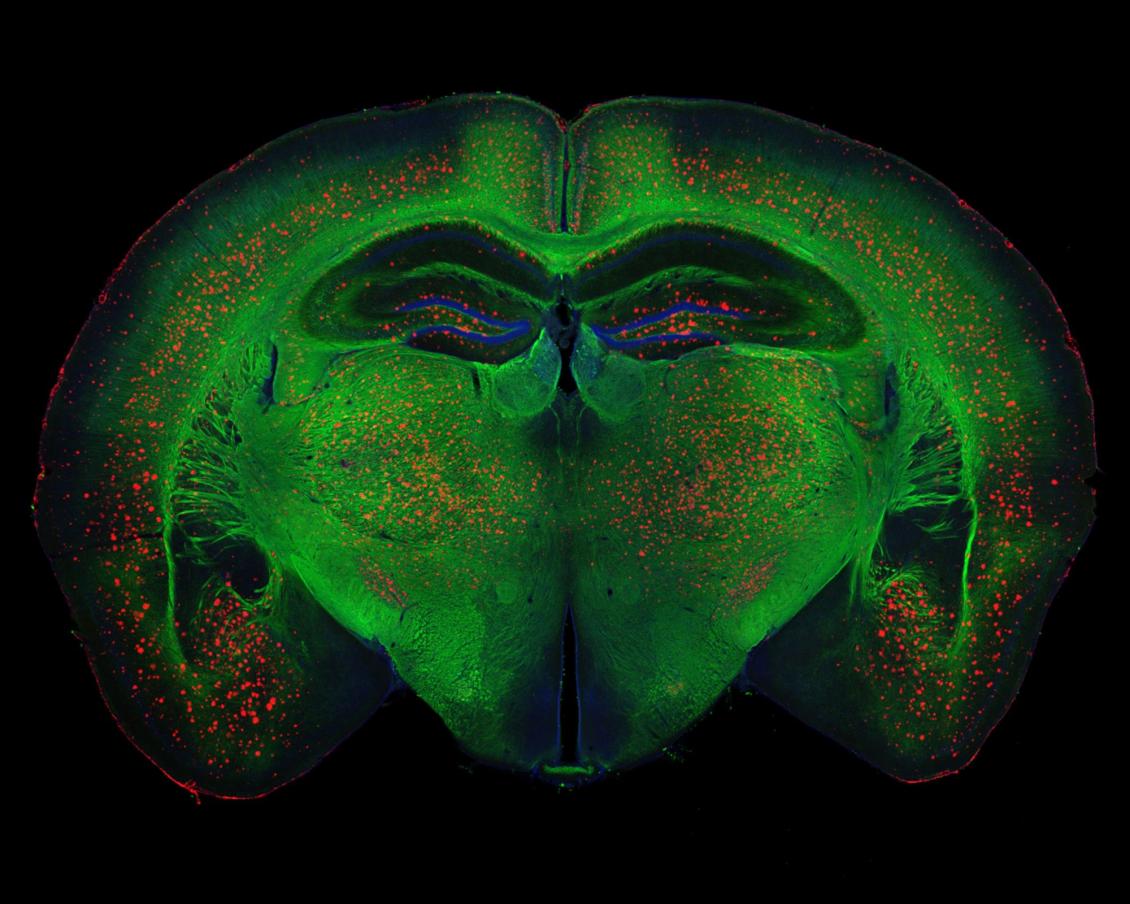

Beta-amyloid plaque deposits (red) disrupt mylelin (green) organization in the brain and activate microglia (orange), driving the inflammation, neurodegeneration, and cognitive disfunction associated with Alzheimer's disease.

Age-related dementia will affect 10 percent of people in the U.S. within their lifetime.

Alzheimer’s disease, the most prevalent type of dementia — and one for which there is no effective treatment or cure — causes a progressive and devastating loss of memory and cognition.

For the past 25 years, efforts to develop a treatment for the disease have focused on the so-called “amyloid cascade hypothesis.” This proposes that amyloid-β (Aβ) peptides build up and clump together to form plaques in the brain, creating a cascade effect that ultimately leads to neuronal death and cognitive dysfunction.